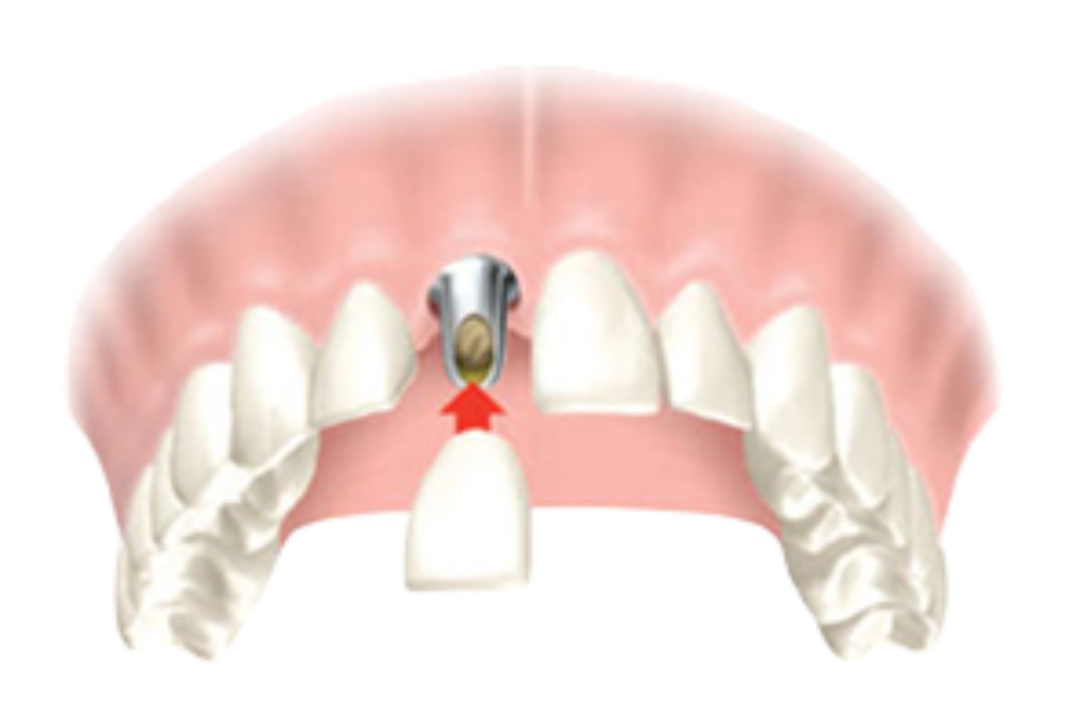

Even a perfectly placed implant can look artificial if the surrounding gums aren’t appropriately managed. Common issues with poor soft tissue management:

❌ Metal showing at the gumline

❌ Uneven gum heights

❌ Tissue recession

❌ Red or black tissue colour

❌ Unnatural contours

✅ Pink, healthy gums that match your natural teeth in color and texture

✅ Proper gum height and contours

✅ Prevents gum recession and metal show-through

✅ Natural look growing

✅ Protects implant from bacteria and bone loss

Once healed, we attach the custom crown, your new tooth that looks, feels, and functions naturally.